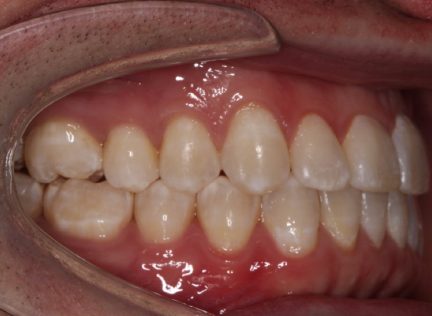

État final

Résultats obtenus

- Relation de classe III maintenue

- Surplomb et recouvrement normaux atteints

- Lignes médianes coïncidentes

- Tous les objectifs du traitement ont été atteints cas

- Des arcades harmoniques ont été réalisées